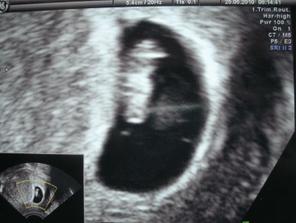

25. května (29. den po ET) jsme na UTZ viděli srdíčko. 54 kg (v lednu 51kg, v dubnu 53kg)

8. června 8+6tt - 2,5 cm, k slzám dojímající ploutvonožec v pohybu. 56kg